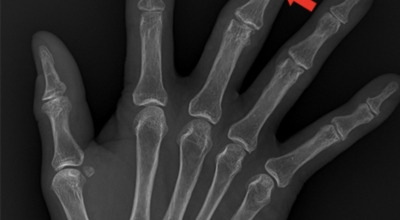

손가락 관절염

관절염은 관절의 연골이 손상되고 염증성 변화가 생기는 질환을 의미합니다. 관절이란 두 개 이상의 뼈가 맞닿는 부위를 말하는데, 이 뼈들의 끝부분은 연골이라는 부드러운 조직으로 덮여 있어 쿠션 역할을 하며 관절이 원활하게 움직일 수 있도록 도와줍니다. 또한 관절은 활막이라는 섬유질 막으로 싸여 있는데, 이 활막은 마찰을 줄여주는 활액을 분비해줍니다.

손가락 관절염의 치료법은 원인에 따라 달라지며, 원인은 크게 두 가지로 나눌 수 있어요. 하나는 관절을 과도하게 사용하거나 노화로 인해 발생하는 퇴행성 관절염, 다른 하나는 자가면역 체계의 이상으로 인해 나타나는 류마티스 관절염입니다. 각각의 원인에 따라 치료 방법도 달라지기 때문에 정확한 진단이 중요합니다.

또한, 손가락의 어느 관절에 부종이 생겼는지에 따라 의심할 수 있는 질환이 달라지는데요, 예를 들어 헤버딘 결절은 손가락 첫 번째 마디(원위지절관절, DIP 관절)에 혹처럼 부풀어 오르는 붓기와 변형이 나타나는 증상입니다. 이 증상이 심해지면 일상생활에 지장을 줄 수 있으므로 초기에 관리와 치료가 필요합니다.